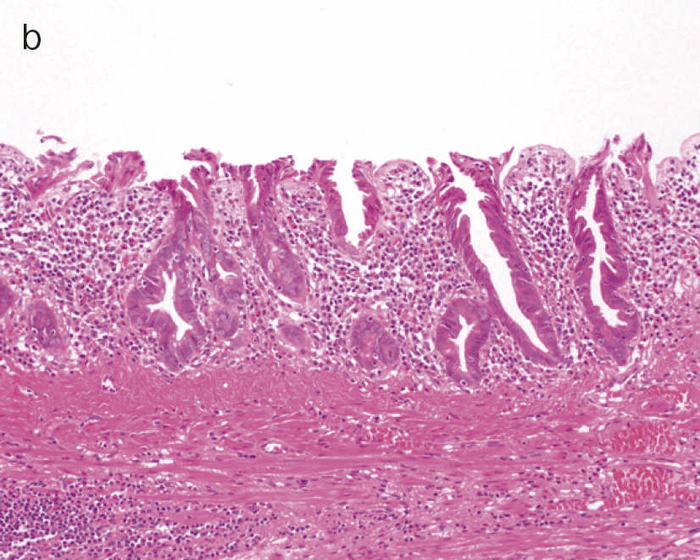

図9 Dysplasiaの代表的な組織像

- LGDの組織像(HE染色):異型腺管では表層への分化傾向が見られる。

- aのp53免疫染色:異型腺管深部側優位にp53蛋白過剰発現が見られる。

- HGDの組織像(HE染色):異型腺管では表層まで核腫大と重積が認められる。

- cのp53免疫染色:異型腺管表層部までp53蛋白の過剰発現が見られる。